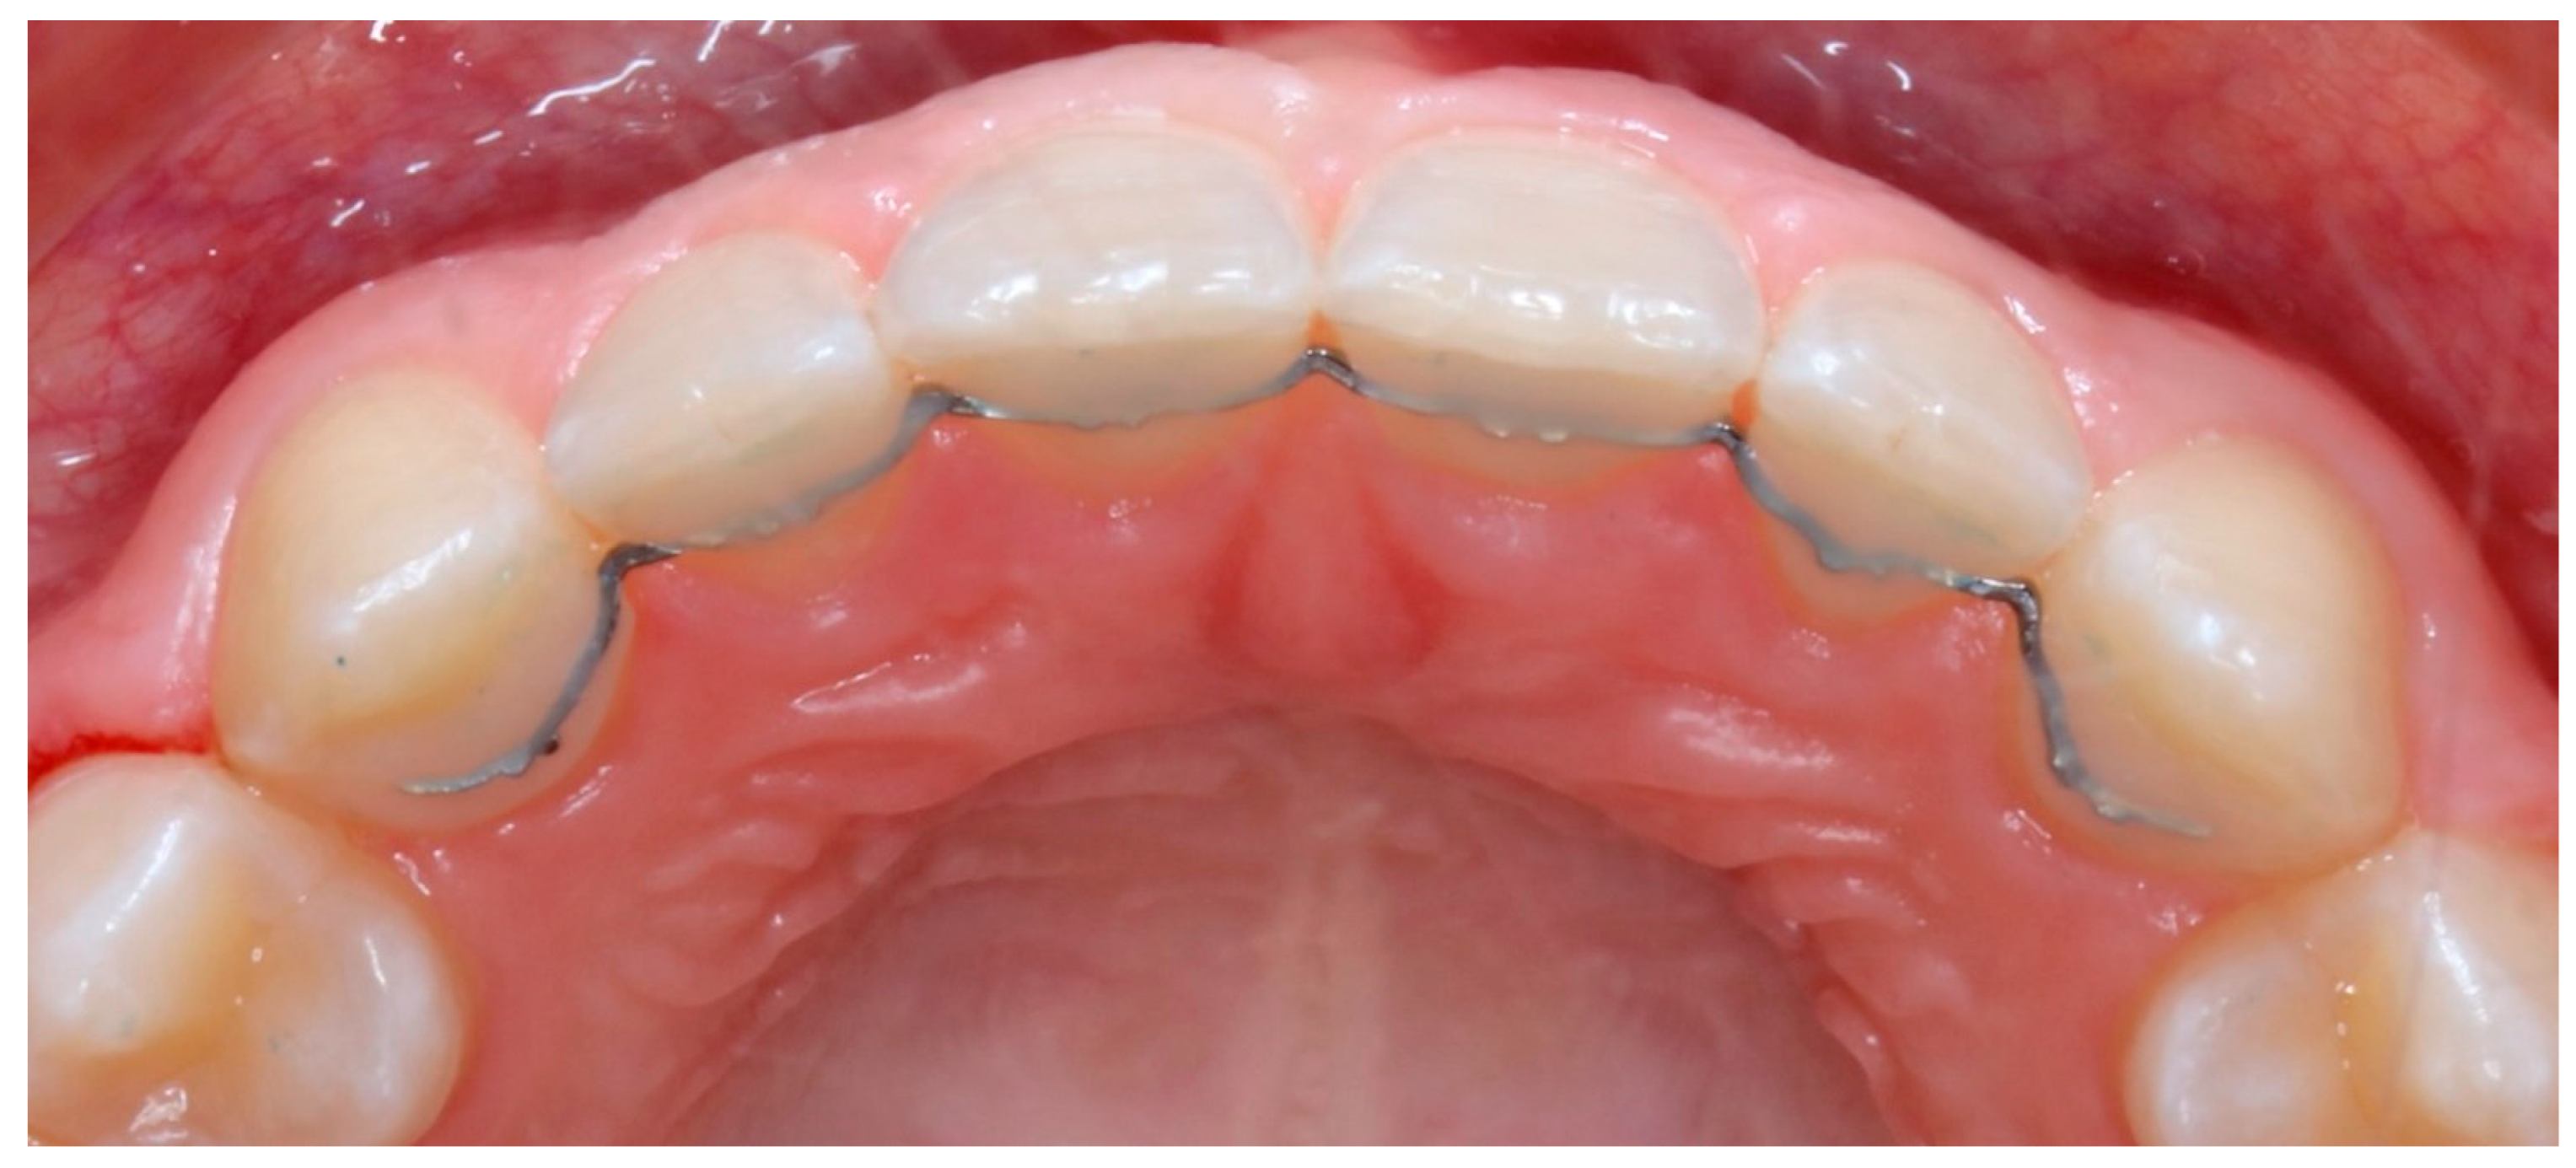

3.3. Maxillary Fixed Retainers